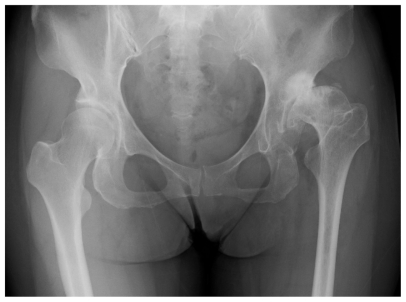

我们报告了一位52岁的女性终末期髋关节骨关节炎伴髋臼发育不良,其生活质量(QOL)通过Kampo治疗得到改善。42岁时,患者出现左髋关节疼痛,髋关节x线检查诊断为早期髋关节骨关节炎。因此,她服用非甾体抗炎药,并接受保守治疗,如饮食和肌肉训练。然而,髋关节疼痛增加,日常生活活动(ADL)在50岁时下降,尽管她继续接受保守治疗。在她52岁时,她向我科咨询日本东方(汉布)医学。邮政寿险局公式;keishikaryojutsubbuto (12Tab/day: Kuracie Co. Ltd.)Boiougito (7.5 g/d: Kuracie Co. Ltd.)。日本),被管理。治疗3个月后,左髋关节疼痛(视觉模拟评分法)减轻,ADL改善。一年后,她的关节症状没有加重,Harris髋关节评分和髋关节骨关节炎的临床评价标准都有所改善。这种疾病的病程取决于患者的生活方式,而Kampo制剂可能提供安全、有效的补充治疗。

We report a 52-year-old female with end-stage osteoarthritis of the hip accompanied by acetabular dysplasia in whom quality of life (QOL) was improved by Kampo treatment.When she was 42 years old, she developed pain in the left hip joint, and early-stage OA of the hip was diagnosed by hip joint x-ray. Therefore, she took NSAIDs, and received conservative therapies such as diet and muscle training. However, pain in the hip joint increased and her activity of daily life (ADL) decreased at the age of 50, although she continued to receive the conservative therapies. At the age of 52, she consulted our department requesting Japanese Oriental (Kampo) Medicine. Kampo formulae; Keishikaryojutsubuto (12Tab/day: Kuracie Co. Ltd. Japan), and Boiougito (7.5 g/day: Kuracie Co. Ltd. Japan), were administered. Treatment for 3 months resulted in a decrease in the left hip joint pain using visual analogue scale (VAS) and improvement of her ADL. One year later, her joint symptoms have not increased, and both the Harris hip score and the clinical evaluation criteria of osteoarthritis of the hip have improved.The course of this disease varies depending on the lifestyle of the patient, and Kampo formulations may offer safe, potent supplemental treatment.